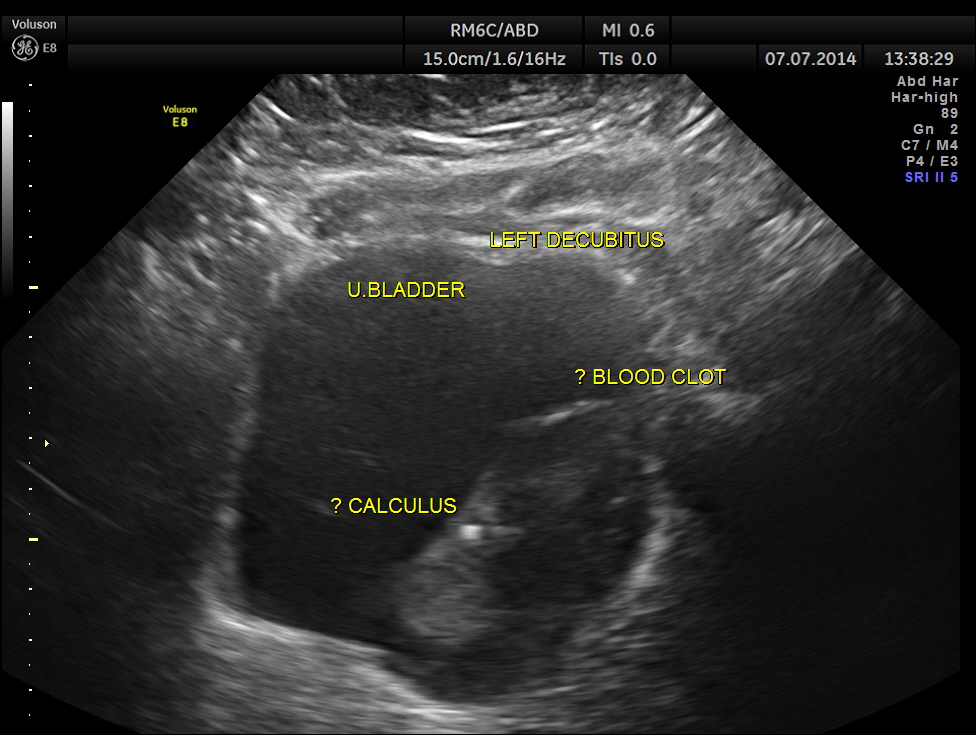

His ultrasound showed the following :

The urinary bladder showed ? mass lesion at first look.

With change of position this ” mass ” was seen to roll within the urinary bladder , suggestive of blood clot.

In this patient the increased vascularity is brought out very well by glass body imaging . Clots of blood seen in the urinary bladder gave the false impression of a mass lesion in the bladder initially.The importance of a dynamic study of turning the patient to the sides should always be remembered.